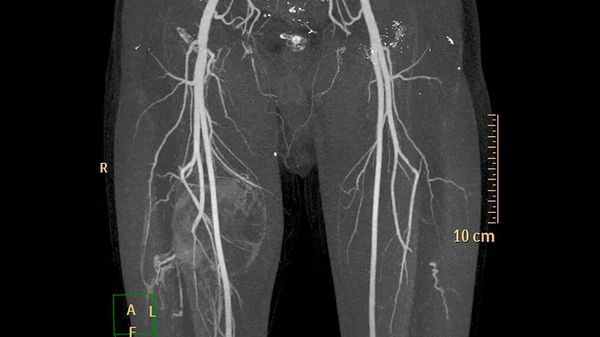

- Томографическая ангиография – предоставляет объёмную визуализацию кровотока в сосудах.

- Магнитно-резонансная ангиография – распознаёт функциональные особенности сосудов и их анатомические изменения.